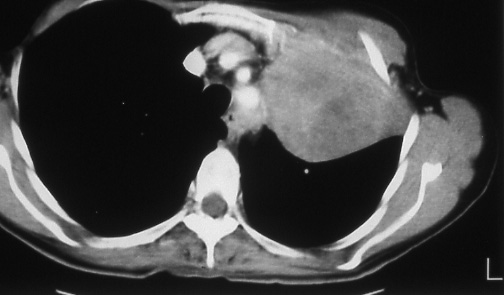

Fig.

43: Computed

tomographic scan of bronchogenic

carcinoma involving the

anterior chest wall.

The medial pleura was

not involved. Metastatic

disease was present in

a normal sized left hilar

lymph node, T3 N1 M0,

stage IIIA disease. |